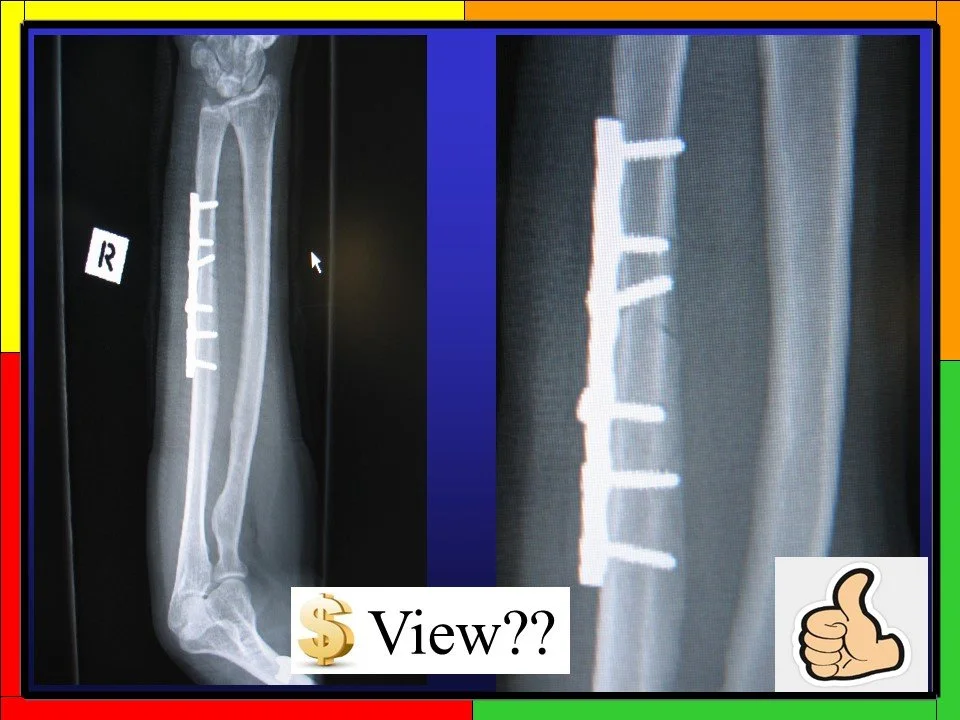

Arthritis

Radiographers